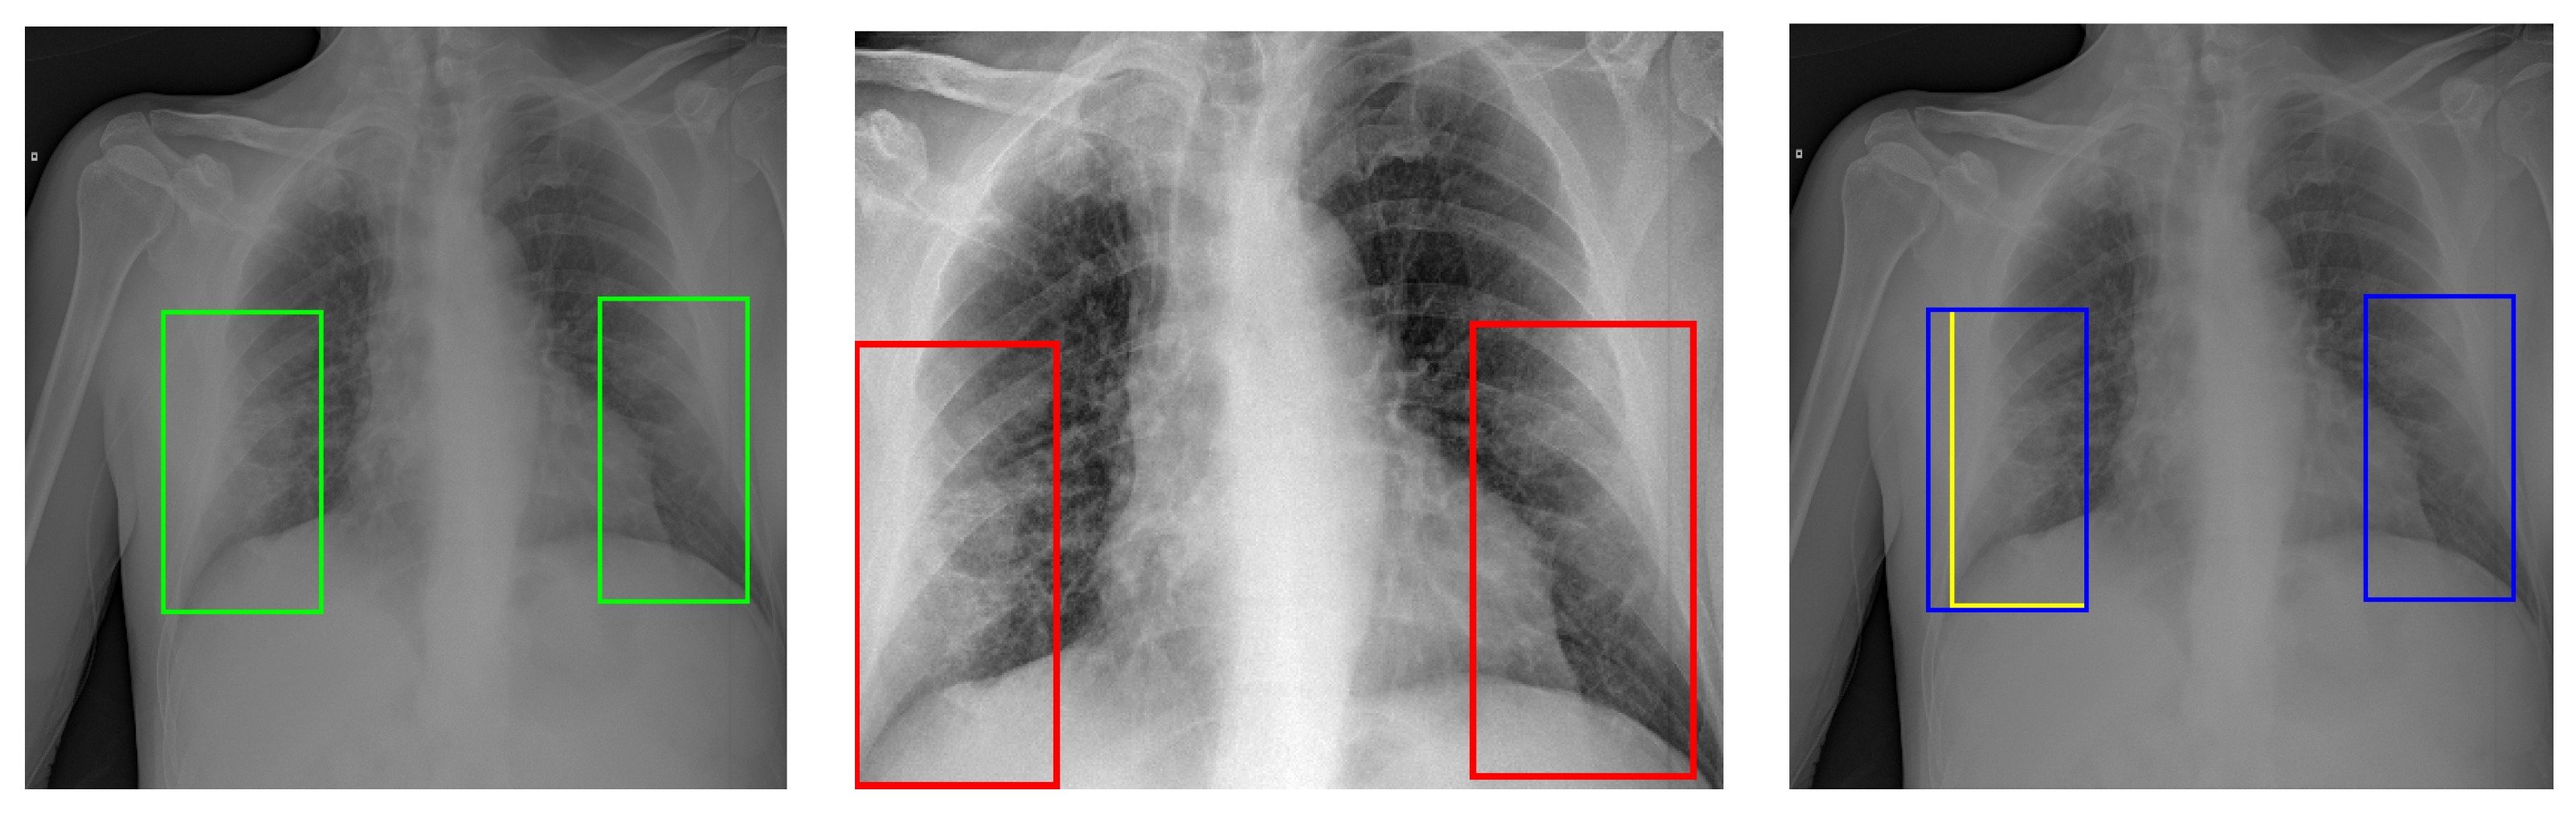

The models developed are grounded on the architectures mentioned above, based on Faster R-CNN, Cascade R-CNN, RetinaNet, and YoloV5. For each architecture, three experiments were carried out according to the pre-processing schemes presented in Section 2.2.1, namely: equalisation; equalisation + cropping; and equalisation + semantic lung segmentation. Furthermore, results were calculated for different evaluation procedures of the bounding boxes: original (Org) (Figure 7 Left), corrected (Corr), and resized (Resz) (Figure 7 Centre and Right).

Figure 7. Bounding boxes before and after the cropping procedure of the images. (Left): Original image with its original bounding boxes (green line). (Centre): Cropped image with resized bounding boxes (red line). The left original bounding box falls partly outside the area cropped. As a result, its size is resized. (Right): Comparison of the original (blue line) and resized (yellow line) bounding boxes.